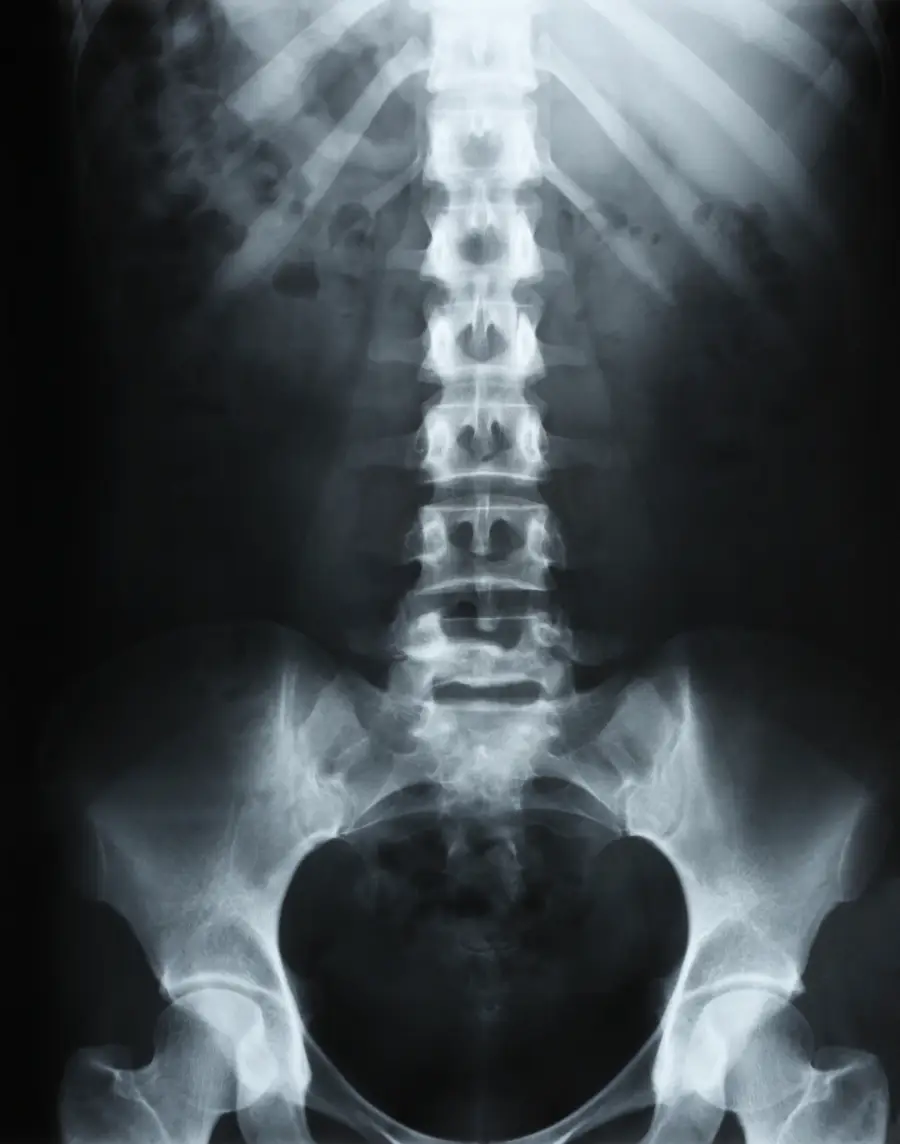

Osteopathic treatment for low back pain

Lower back pain is one of the most common reasons for consulting an osteopath. It refers to any pain localised in the lumbar region, that is, the lower part of the back between the last ribs and the pelvis. Lower back pain can be acute (lumbago), subacute or chronic, and it affects a large majority of the population at some point in their lives. Osteopathy offers a manual approach aimed at identifying and treating the mechanical causes of these complaints.

The physical examination includes a global postural evaluation, mobility tests of the lumbar spine, pelvis, hips and thoracic spine, as well as neurological tests if radiation into the lower limb is reported. This examination allows the osteopath to establish an osteopathic diagnosis and define an appropriate treatment plan.